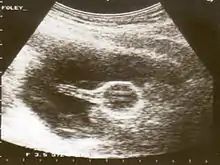

Ultrasound image of a Foley catheter